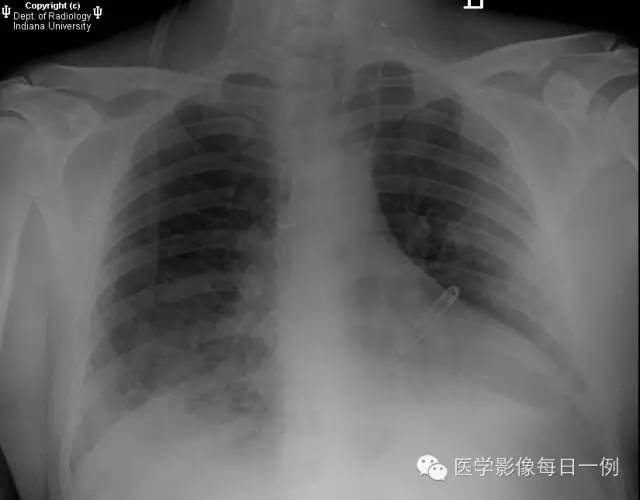

胸部正位片

【答案】1.C注释:主要表现为双肺基底部肺泡透光度减低,边界模糊。

胸片示双肺肺泡性病变,主要为基底部肺泡性疾病或渗出。